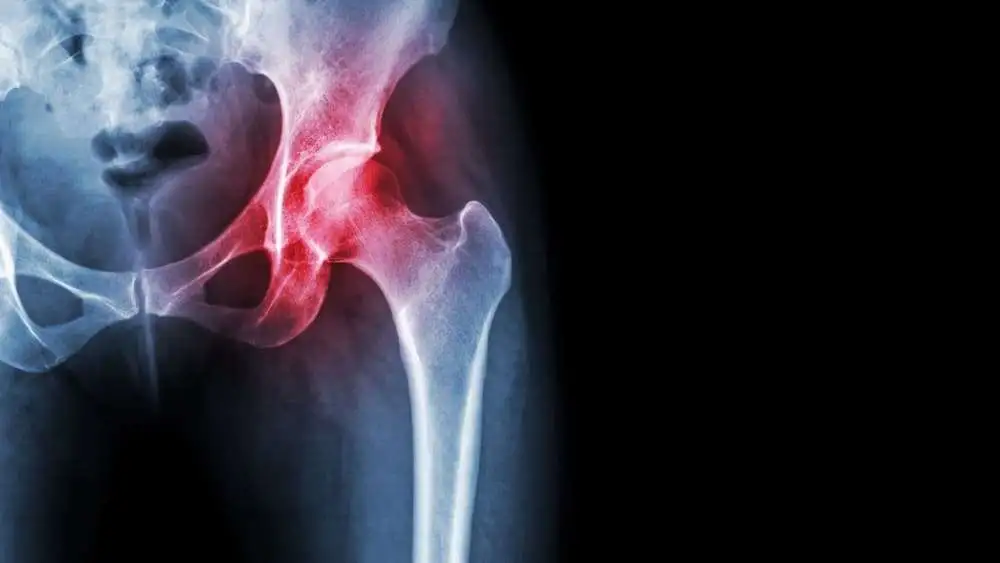

This study focused on comparing the fascia-iliaca compartment block and the intra-articular hip injection concerning pain management and the need for further systemic analgesia in the pre-operative phase of intracapsular hip fractures.